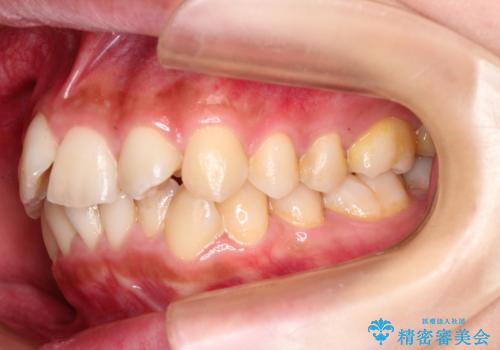

左上の前から2番目の歯が通常とは異なる形態をしており、左右対称にすることはできませんでしたが、インビザラインで周りに気づかれることなく矯正治療をおえることができ、満足していただけました。